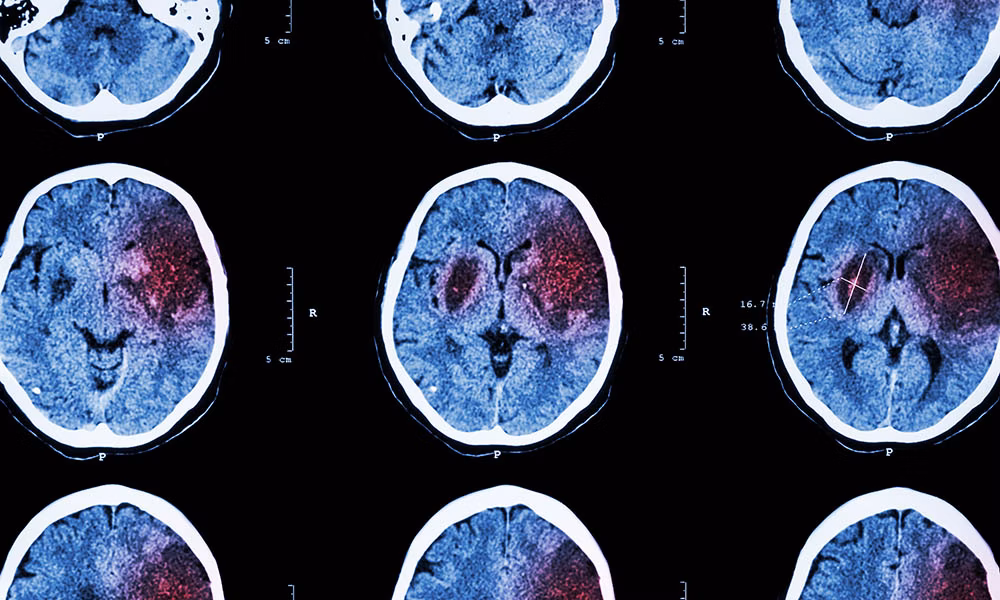

Damit eine gezielte Therapie erfolgen kann, muss herausgefunden werden, ob eine Minderdurchblutung oder Hirnblutung besteht. Dies geschieht meist durch bildgebende Verfahren, z.B. eine Computertomographie (CT) und/oder Magnetresonanztomographie (MRT) des Gehirns.

Bei einem Schlaganfall kommt es zu einer Störung der Blutversorgung des Gehirns (aufgrund Minderdurchblutung oder Hirnblutung). Die Diagnosestellung erfolgt neben der klinisch-neurologischen Untersuchung mittels bildgebender Verfahren (CT, MRT).